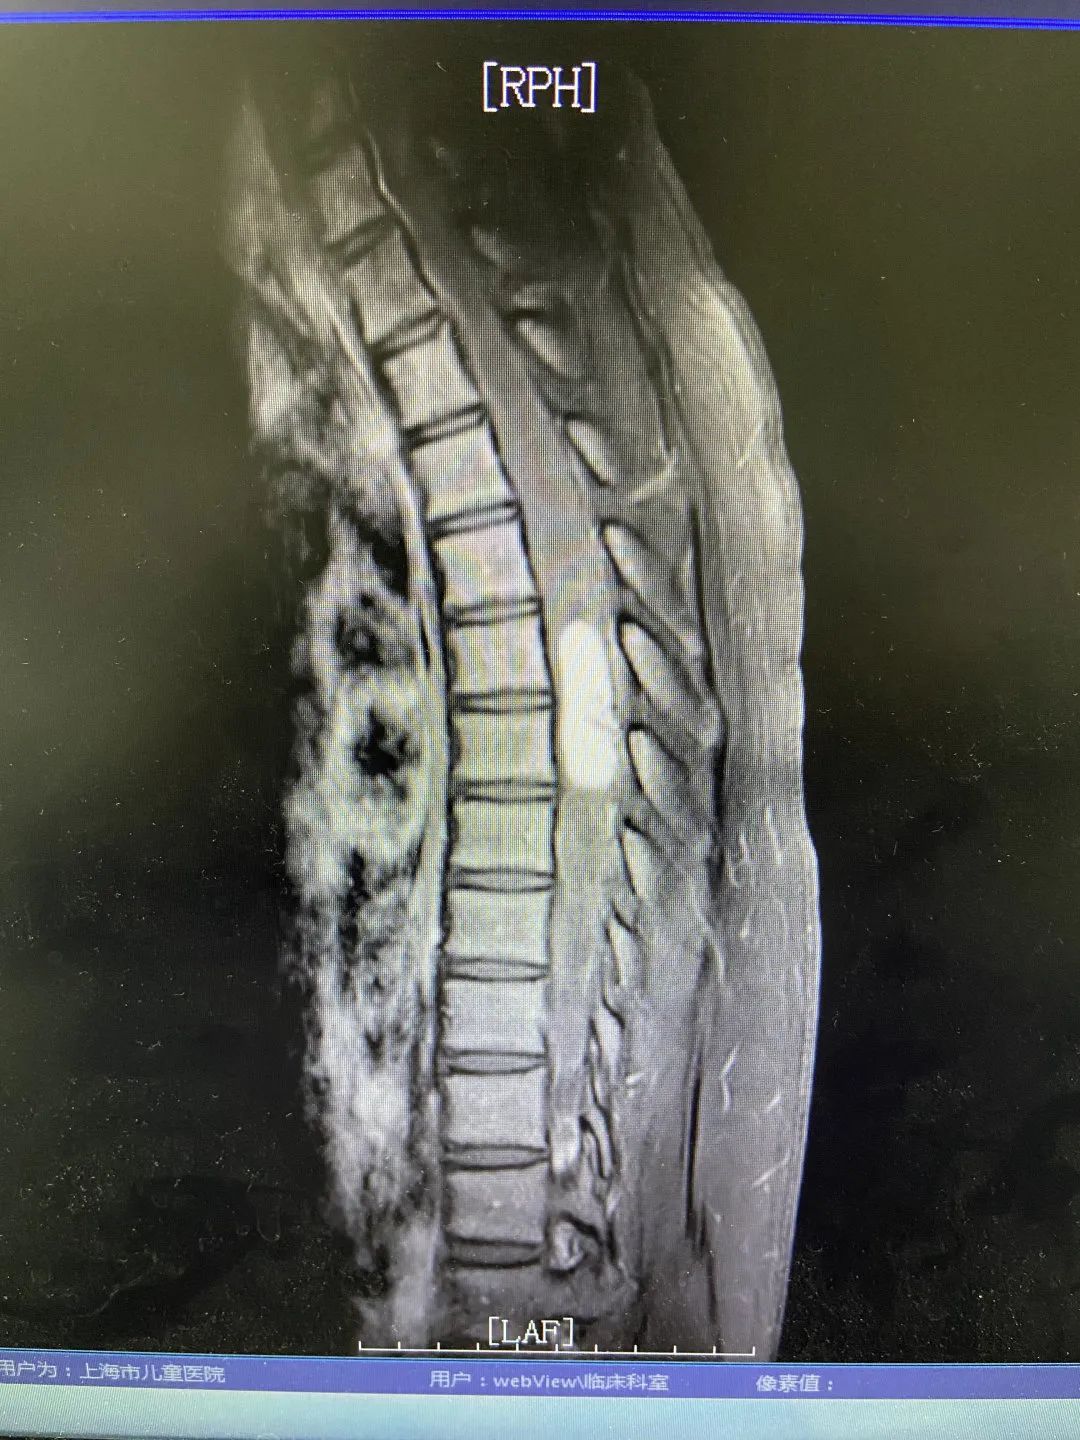

经详细检查诊断,清清所患的疾病是脊髓血管母细胞瘤,是一种由脑神经和脊髓神经产生的高度血管分化的良性肿瘤。虽说是良性,但随着病情的发展,肿瘤越长越大,会压迫脊髓神经,继而造成相应的功能受损。而且清清的肿瘤位于上胸段,如果不尽快手术切除,持续增大的肿瘤会引起严重的并发症,如肿瘤平面以下肢体瘫痪、尿失禁等。因此,为了避免病情的恶化,需要尽快开展手术,而在切除肿瘤的同时保证脊髓功能的完好,又为这台手术的开展增加了很大难度。

为此,我院神经外科医疗团队采用国内外最先进的技术和方法,制定出一套详尽的治疗方案;并在术中运用持续同步的感觉诱发电位(SEPs)和动作诱发电位(MEPs)的监测,加上专职的神经电生理监护师保驾护航,最终手术顺利完成,完整切除肿瘤,清清的病情得到了有效控制,且术后身体运动功能良好,没有出现任何手术相关并发症。